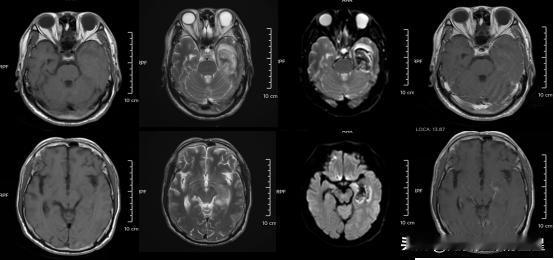

太吓人了!30岁小伙熬夜后智力一夜回到3岁,医生发现近一个月竟有8个年轻人中招,最小的才16岁! 这事就发生在宁波一家医院,这些年轻患者都是脑膜炎,平均年龄才26岁。他们有个共同点——长期熬夜,作息完全乱套。最惨的那个30岁小伙子,现在连基本生活都不能自理,智商真的退化到幼儿水平。 说真的,看到这个新闻我后背发凉。咱们年轻人现在谁不熬夜?刷短视频、打游戏、追剧,一抬头又凌晨两三点了。总觉得年轻就是资本,谁能想到熬夜的代价这么惨重? 免疫力这东西,平时感觉不到,一旦垮掉,什么病都找上门。脑膜炎真不是闹着玩的,严重起来会留下终身后遗症。 看完这条新闻,你还敢继续熬夜吗?来说说你昨晚几点睡的?现在放下手机还来得及!熬夜损伤大脑 长年熬夜后遗症 熬夜肝会怎么样